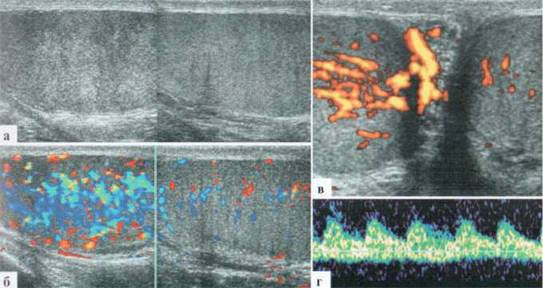

Орхит у детей встречается редко, чаще в подростковом возрасте, но зафиксирован и у новорожденных. Причина заболевания не всегда ясна, клинико-лабораторное подтверждение инфекции мочевыводящих путей, которой отводится известная роль в генезе орхитов и эпидидмитов, имеет место далеко не всегда. Характерны весьма разнообразные изменения структуры яичка в В-режиме: от редко выраженных до практически не дифференцируемых. В большинстве случаев имеет место некоторое увеличение яичка в размерах, преимущественно — в толщину, при этом оно приобретает шаровидную форму. Эхогенность паренхимы может оставаться нормальной, может диффузно понижаться. Всегда имеется значительное усиление сосудистого рисунка в паренхиме яичка. Часто определяется некоторое снижение RI артериального тестикулярного кровотока, но, строго говоря, количественная оценка тестикулярного кровотока при гиперемии яичка у детей с орхитами редко дает принципиально новую информацию для оценки состояния пораженного органа. Часто определяется утолщение оболочек яичка за счет их отека и небольшое количество жидкостного содержимого в оболочках (рис. 2.3.1).

Рис. 2.3.1. Орхит слева у ребенка 11 лет: а, б — правое неизмененное яичко 32x15 мм; в, г — левое яичка увеличено в размерах до 42x26 мм, паренхима гомогенная, без значительных структурных изменений, резко выраженное диффузное усиление сосудистого рисунка

Весьма демонстративным является поперечное сканирование мошонки, когда датчик располагается перпендикулярно ее шву, и в поле сканирования попадают одновременно оба яичка или хотя бы их внутренние фрагменты. Изменение формы яичка и интенсивности интратестикулярного сосудистого рисунка не вызывают сомнения (рис. 2.3.2).

Рис. 2.3.2. Поперечное сканирование по передней поверхности мошонки у ребенка 13 лет с правосторонним орхитом с одновременной визуализацией фрагмента правого (D) и левого (S) яичек